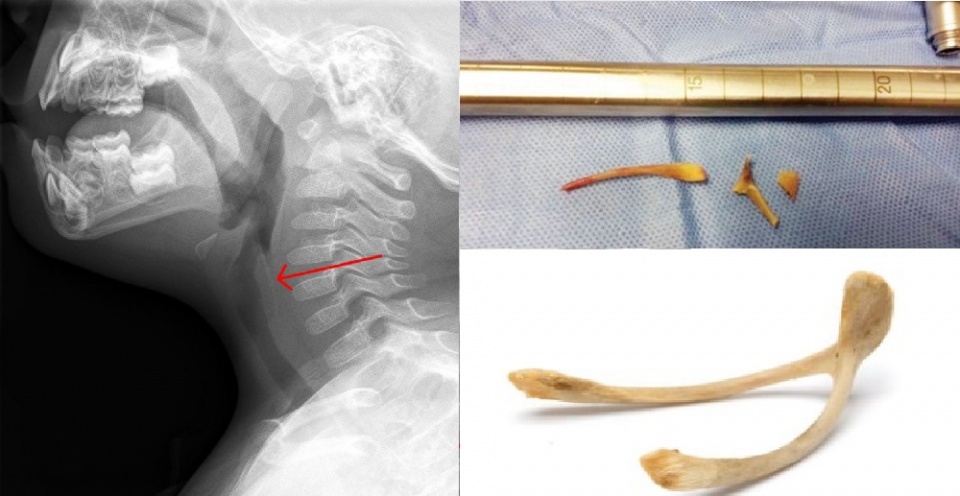

وطلبت وانغ جيونغ، نائب رئيس قسم جراحة القلب والصدر في مستشفى جامعة غوانزو الصينية، مجموعة من الأشعة المقطعية التي كشفت عن وجود جسم غريب عالق في الرئة اليمنى للفتاة.

وأجرى الجراح يانغ مينغ عملية منظار للفتاة لتحديد الجسم الغريب، استغرقت 30 دقيقة، إذ أخل أنبوبًا به ضوء وكاميرا صغيرة من فمها مرورا بالشعب الهوائية وصولاً إلى الرئتين.

وتمكن الدكتور مينغ من العثور على الجسم الغامض في رئة الفتاة اليمنى، وعندما أخرجها تبين أنها قطعة من عظم الدجاج بطول 2 سم.